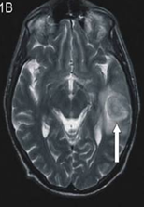

A Case of Unusual Presentation of Transverse and Sigmoid Sinus Thrombosis in Puerperium

Shruthi Kallesh, Mangala Gowri, Sreelatha Sampath Kumar*, Vedavathy Nayak, Vandana Ambasta, Sumaya, Kavitha, Nandini Swamy